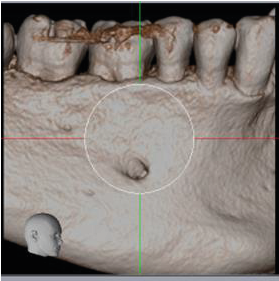

From a surgical perspective, the root of the supernumerary tooth is straight and its apex contacts the ID canal at the point at which the mental canal is given off (images 5 and 6). The only potential risk would be with downward pressure. In a surgical context there is a potential risk with any applied downward pressure.

6. Volume-rendered image of buccal surface of mandible showing mental foramen position and two Maximum Intensity Projection images with the ID and mental canals marked.

Volume-rendered image